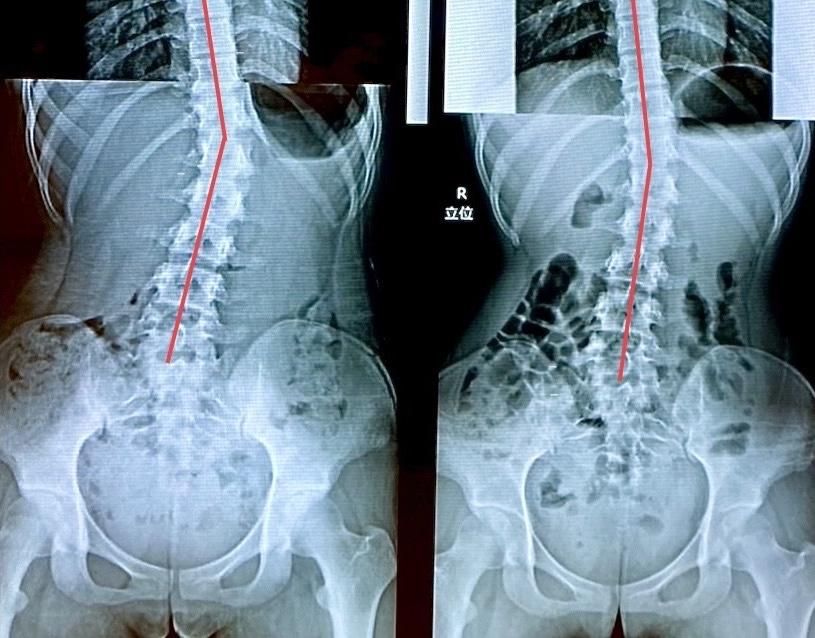

中〜高校生の改善例(女の子)

病院では「定期的な経過観察が必要」と言われ、ただただ経過観察をしていく中で、「他に何かできることはないのか…」「進行度合いの確認だけでなく根本的に改善させるような方法はないのか…」との親御様の切なる思いからインターネットで検索され当院に来院されました。現在も尚、病院でのリハビリ指導と当院でのカイロプラクティックケアに運動指導などを行いながら、さらなる改善へ向けて取り組まれています。

※これは個人の感想と画像の結果であり施術の効果を保障するものではありません。また効果には個人差があります。